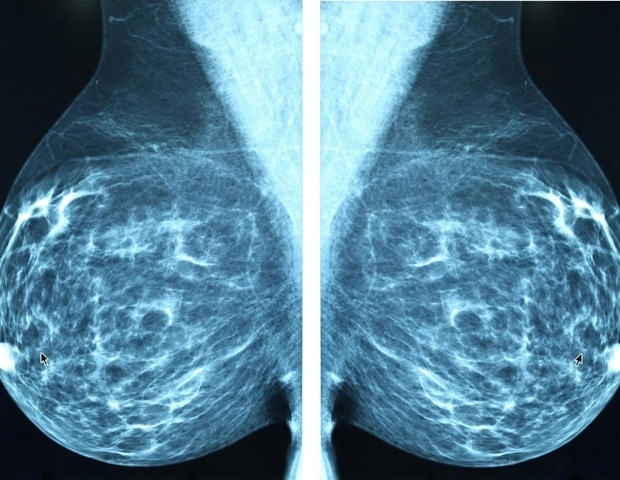

Μια πρόσφατη μελέτη που παρουσιάστηκε στο San Antonio Breast Cancer Symposium (SABCS) αποκάλυψε ότι η χρήση θεραπείας ορμονών εμμηνόπαυσης (MHT) δεν σχετίζεται με αυξημένο κίνδυνο καρκίνου του μαστού σε γυναίκες που φέρουν κληρονομικές μεταλλάξεις στα γονίδια BRCA1 ή BRCA2. Τα αποτελέσματα της μελέτης είναι ιδιαίτερα σημαντικά για τις γυναίκες αυτές, οι οποίες συχνά συμβουλεύονται να υποβληθούν σε προληπτική αφαίρεση ωοθηκών και σαλπίγγων για να μειώσουν τον κίνδυνο καρκίνου των ωοθηκών και των σαλπίγγων.

Η μελέτη περιλάμβανε μια προοπτική ανάλυση, όπου οι ερευνητές προσπάθησαν να αναπαραστήσουν τις συνθήκες μιας κλινικής δοκιμής, αναλύοντας δεδομένα από γυναίκες που είχαν υποβληθεί σε εμμηνόπαυση (κυρίως λόγω χειρουργικής επέμβασης) και τη χρήση MHT. Οι συμμετέχουσες που είχαν ιστορικό καρκίνου ή είχαν υποβληθεί σε διπλή μαστεκτομή αποκλείστηκαν. Δημιουργήθηκαν 676 ζευγάρια γυναικών που χρησιμοποίησαν και δεν χρησιμοποίησαν MHT, με κριτήρια αντιστοίχισης τα γονίδια BRCA1 ή BRCA2, το έτος γέννησης και την ηλικία εμμηνόπαυσης. Οι συμμετέχουσες κυμαίνονταν από 22 έως 76 ετών, με μέση ηλικία τα 43,8 έτη.

Οι γυναίκες που χρησιμοποίησαν MHT έλαβαν διάφορες μορφές: μόνο οιστρογόνα, μόνο προγεστερόνη, συνδυασμένα οιστρογόνα και προγεστερόνη, tibolone ή συνδυασμένα οιστρογόνα και bazedoxifene. Μετά από μέση παρακολούθηση 5,6 ετών, οι ερευνητές διαπίστωσαν ότι οι περιπτώσεις καρκίνου του μαστού ήταν σημαντικά λιγότερες στις γυναίκες που χρησιμοποίησαν MHT, με 87 περιπτώσεις στην ομάδα που χρησιμοποίησε MHT σε σύγκριση με 128 στην ομάδα που δεν χρησιμοποίησε.

Ελπιδοφόρα αποτελέσματα

Αναλύοντας τα δεδομένα με βάση τη μορφή της MHT, οι περισσότεροι τύποι δεν παρουσίασαν καμία συσχέτιση με τον κίνδυνο καρκίνου του μαστού. Ωστόσο, δύο συγκεκριμένες μορφές συσχετίστηκαν με μειωμένο κίνδυνο. Οι γυναίκες που έλαβαν μόνο οιστρογόνα είχαν 63% λιγότερες πιθανότητες να αναπτύξουν καρκίνο του μαστού σε σύγκριση με τις γυναίκες που δεν χρησιμοποίησαν MHT. Εντυπωσιακά, από τις 43 γυναίκες που έλαβαν συνδυασμένα οιστρογόνα και bazedoxifene, καμία δεν ανέπτυξε καρκίνο του μαστού. “Αν και βασίζεται σε μικρότερες ομάδες, αυτό είναι σίγουρα ένα ενθαρρυντικό και σημαντικό εύρημα,” κατέληξε η Kotsopoulos.